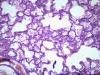

Подскажите как назвать данную пневмонию. По закону парных случаев, на данный момент у меня два разных случая с одинаковой морфологией. В морфологии в альвеолах эозинофильное содержимое, слущенные альвеолоциты, гигантские, многоядерные клетки, выраженный геморрагический компонент, местами немного лейкоцитов, свертки фибрина. Обширные свертки в бронхах. Очень похоже на вирусную, но как ее может назвать морфолог?

Интерстициально-десквамативная.

+ местами похоже на гиалиновые мембраны и в капиллярах межальвеолярных перегородок встречаются мегакариоциты.